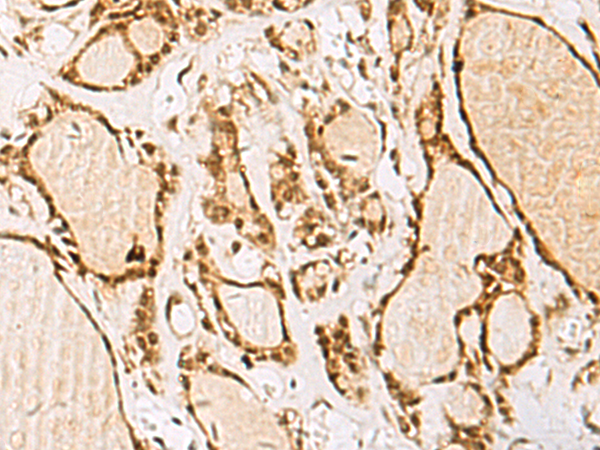

IHC positive control: |

Human thyroid cancer |

IHC Recommend dilution: |

50-200 |